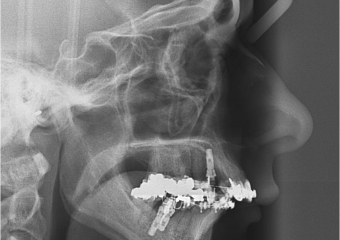

Telerradiografia inicial

Telerradiografia após a cirurgia